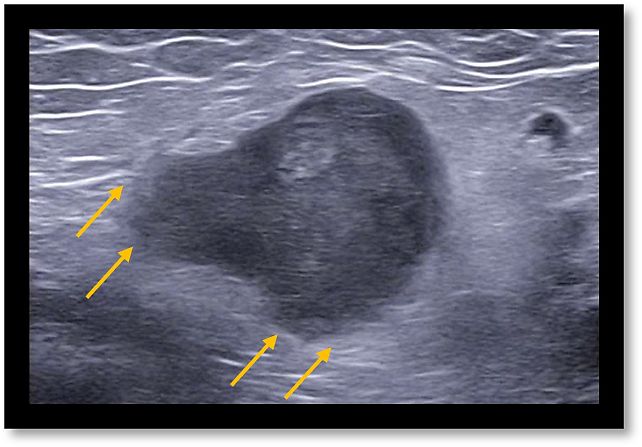

- Capsular interruption: a break in the hyperechoic capsule suggests extracapsular tumor spread (Figure 7).

7

Interruption of hyperechoic lymph node capsule (arrows).